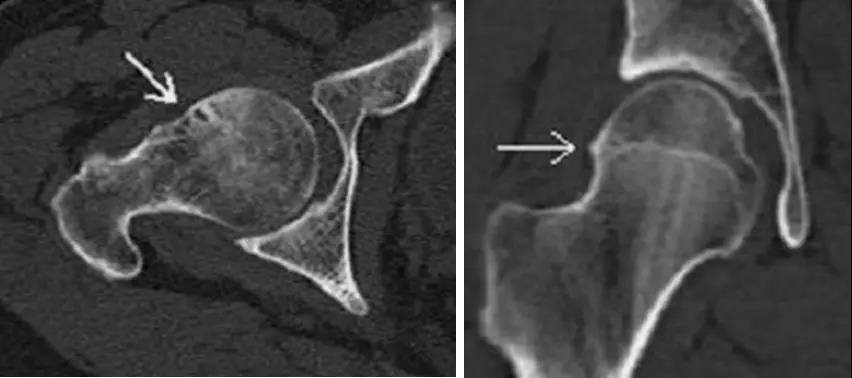

凸轮撞击型FAI▼

- 股骨头颈联合处前上缘骨性突起。

- 非圆形的股骨头。

- 股骨头颈联合处前缘骨性突起、骨质硬化,α角增大。

钳夹撞击型FAI▼

- 横断面显示髋臼后倾:正常髋臼连线与水平线呈钝角;呈锐角,提示髋臼后倾。